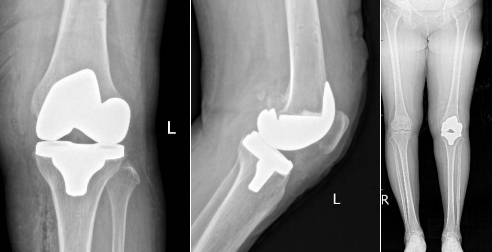

術(shù)后患者的關(guān)節(jié)力線恢復(fù)平衡

患者術(shù)后DR